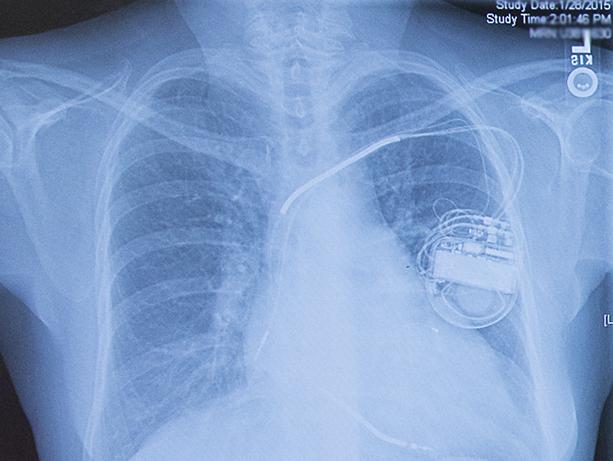

ICDs are small implanted devices that deliver electrical shocks to the heart to help control life-threatening irregular heartbeats, or arrhythmias. (Pacemakers are a different implanted device which gives off low-energy electrical pulses to treat less-dangerous heart rhythms.) ICDs are standard care to prevent sudden death in patients at high risk of cardiac arrest.